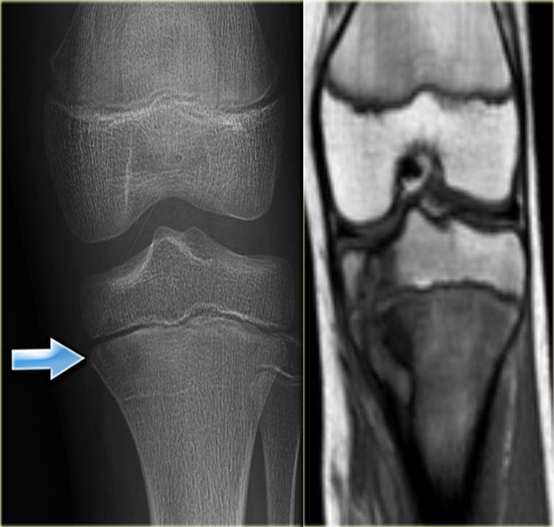

Compare X-ray and MRI in this case of acute osteomyelitis.

- It is difficult to be seen on plain x-ray.

- The extent of disease is well demonstrated by MRI

(A) Â An initial films reveals no abnormality

(B) A film taken 3 weeks later shows some destruction of the upper end of the tibia and an extensive periosteal reaction along the tibia, particularly the medial side (arrow).